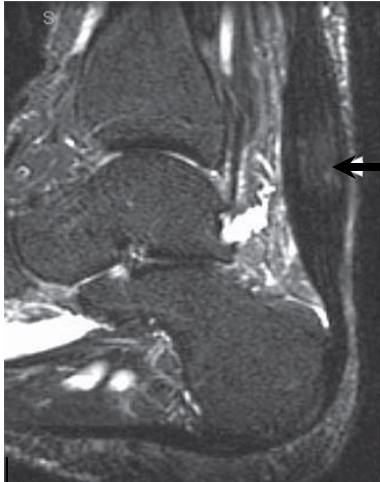

Inflammation of the Achilles’ tendon where it inserts into the calcaneus (heel bone) is known as insertional tendonitis. It is often associated with an abnormal bony prominence just deep to the tendon known as Haglund’s deformity. This may play a role in rubbing on the deep aspect of the tendon to cause pain and inflammation in the tendon and surrounding soft tissues. If the associated bursitis becomes swollen enough, it can also rub on footwear or even prevent the wearing of certain shoes.

Haglund’s deformity